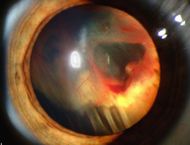

| Slit lamp photograph showing retinal detachment. | |